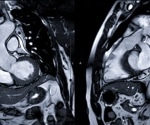

Cardiac MRI of individuals with acute or post-acute COVID-19